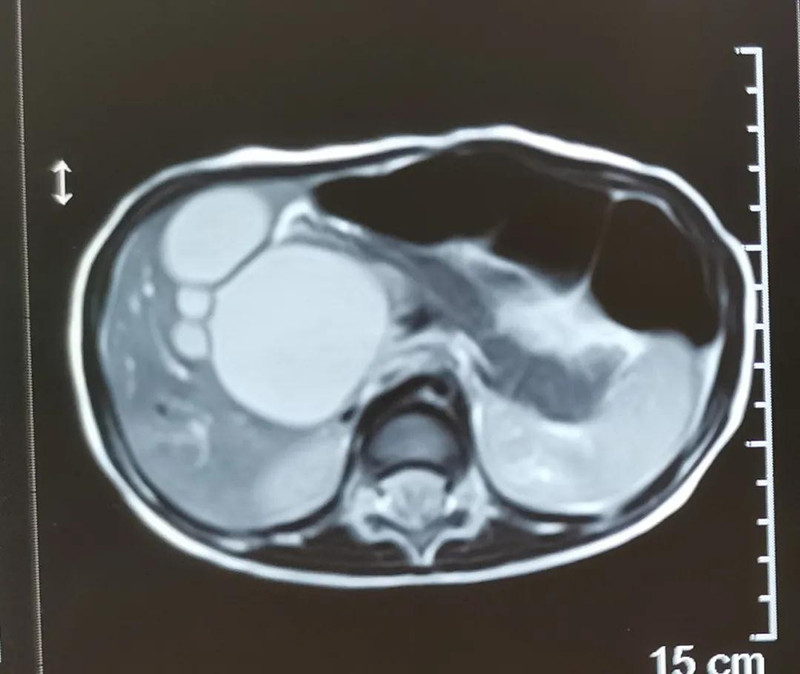

严重:胆总管病变,有癌变隐患

最近半个月,长春市26个月女宝馨馨(化名)脸色不好,全身发黄严重,还伴随发烧。9月23日,馨馨被家人带到德州扑克游戏网 诊治。经检查,馨馨全身发黄是因为患有黄疸,而黄疸的出现是因为胆总管发生病变,“胆总管呈现囊性扩张,下边出口被堵住,胆汁进不到肠腔里,导致孩子出现黄疸、肝功不好、白土便症状。而且胆总管胀大后,还有癌变的风险,”普外、新生儿外科主任崔钊说,馨馨需要尽快手术。为了减少损伤,崔钊主任团队制定的方案是单孔腹腔镜下胆总管囊肿根治手术。